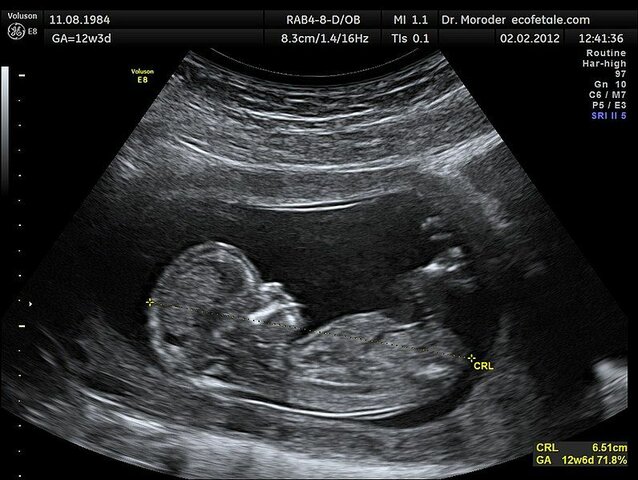

• Ecografía

Ecografía

En 1957, el ingeniero Tom Brown y el Dr. Donald, construyeron un escáner bidimensional, evitando así la técnica de inmersión. Tomaron fotos y publicaron posteriormente el estudio en 1958.